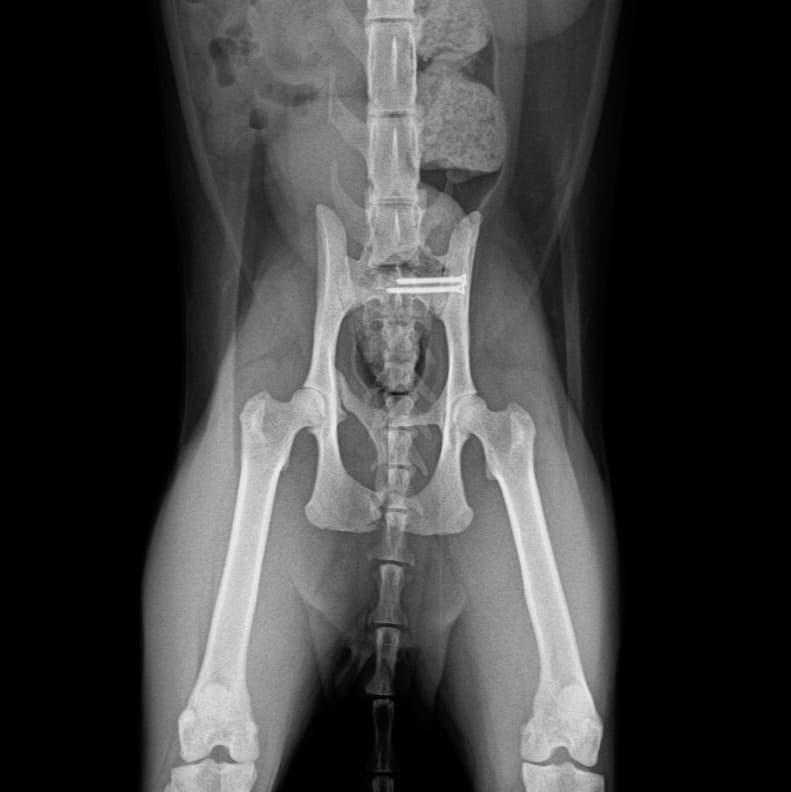

동탄 1 신도시 최초 Aquilion CX/128 slice CT를 동물병원에 도입하였습니다. 최고 사양 CT 모델 Aquilion CX/128 slice를 활용하여 0.5 mm의 얇은 128개의 단면 영상을 신속히 획득 할 수 있어 마취 시간을 단축시킬 수 있습니다. 또한, 128 슬라이스의 고화질의 CT 영상을 통해 영상 왜곡을 최소화하고 X-ray에서는 확인하기 힘든 5 mm 이하의 미세 병변도 확인이 가능하여 정확한 진단을 할 수 있습니다. 심화 진단이 필요한 경우, 조영제 인젝터를 통한 동맥기 촬영으로 종양 유래 확인, 간 질환 진단, 심혈관계 진단이 용이합니다. 저희 동탄시티동물의료센터에서는 본원 환자뿐 아니라 1차 동물 병원과의 CT 촬영 의뢰 시스템을 통해서 원활한 협진이 가능하도록 최선을 다하고 있습니다.

0164 채널 CT 촬영을 통해서 신속하게 고화질 영상을 얻어, 종양 유래 확인 및 전이 평가, 간문맥단락증(PSS), 선천적 뼈 기형과 같은 심화된 진단을 할 수 있습니다.